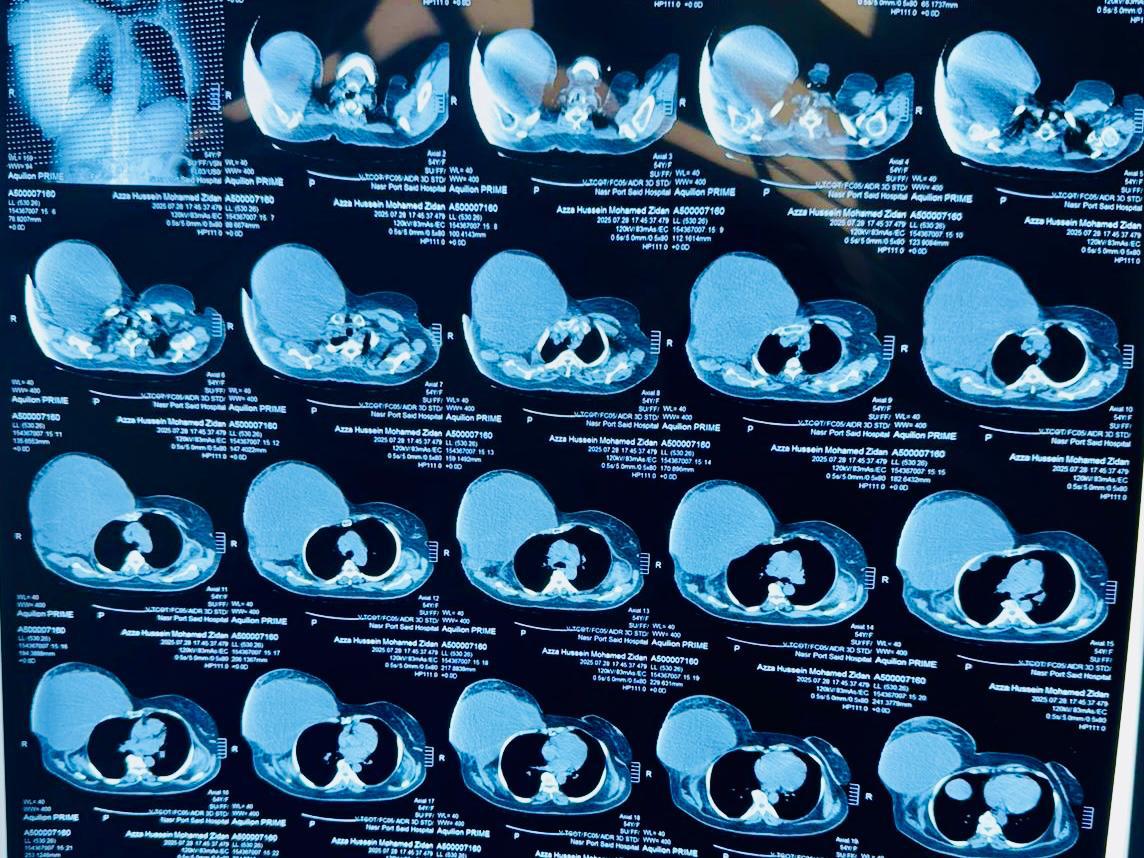

أعلنت الهيئة العامة للرعاية الصحية، برئاسة الدكتور أحمد السبكي، رئيس الهيئة والمشرف العام على مشروع التأمين الصحي الشامل، عن نجاح فريق طبي بمستشفى السلام ببورسعيد – أحد مستشفيات الهيئة – في إجراء عملية جراحية دقيقة ونادرة لسيدة خمسينية، تضمنت استئصال ورم ضخم يزن ستة كيلوجرامات من جدار الصدر الأمامي مع إعادة بنائه.